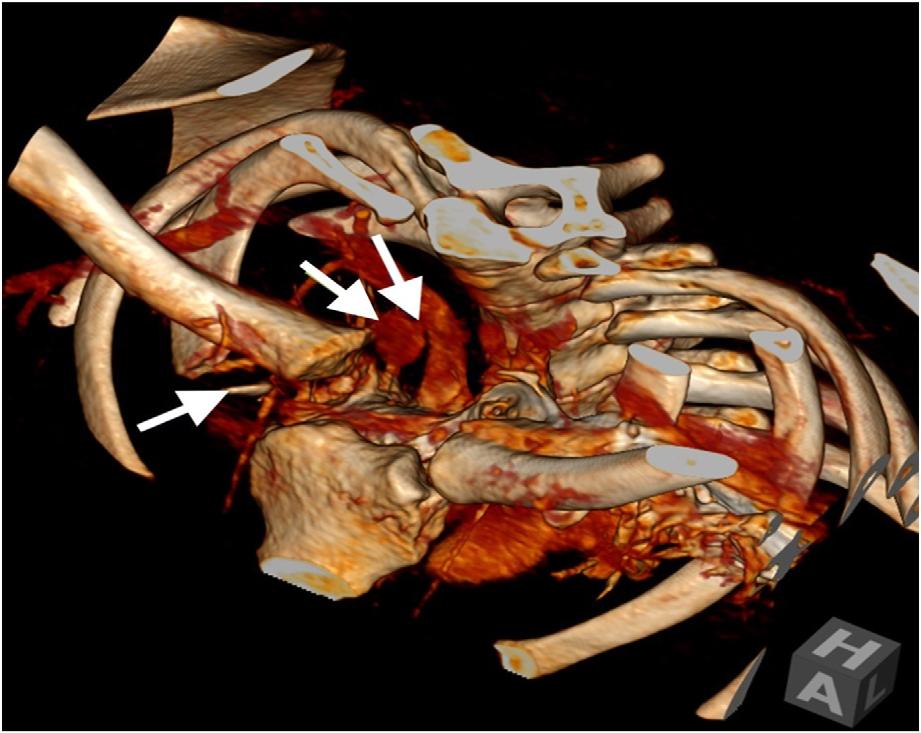

125 Inferior Pancreaticoduodenal Artery Pseudoaneurysm Causing Biliary Obstruction: A Case Report

Patrick Meloy, Will S. Lindquester, Jeffrey Stebbins, Elaine Bromberek